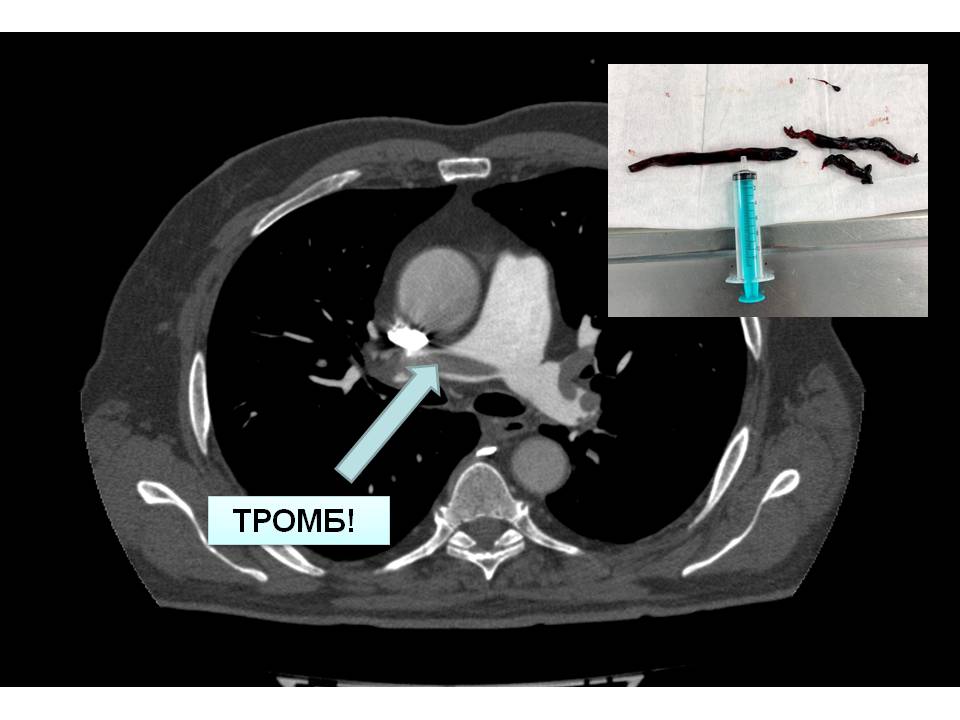

Хирурги извлекли из легочной артерии пациента тромбы длиной более 10 см

Хирурги в Чувашии извлекли 10-сантиметровые тромбы из легочной артерии пациента |

Хирурги извлекли из легочной артерии пациента тромбы длиной более 10 см |